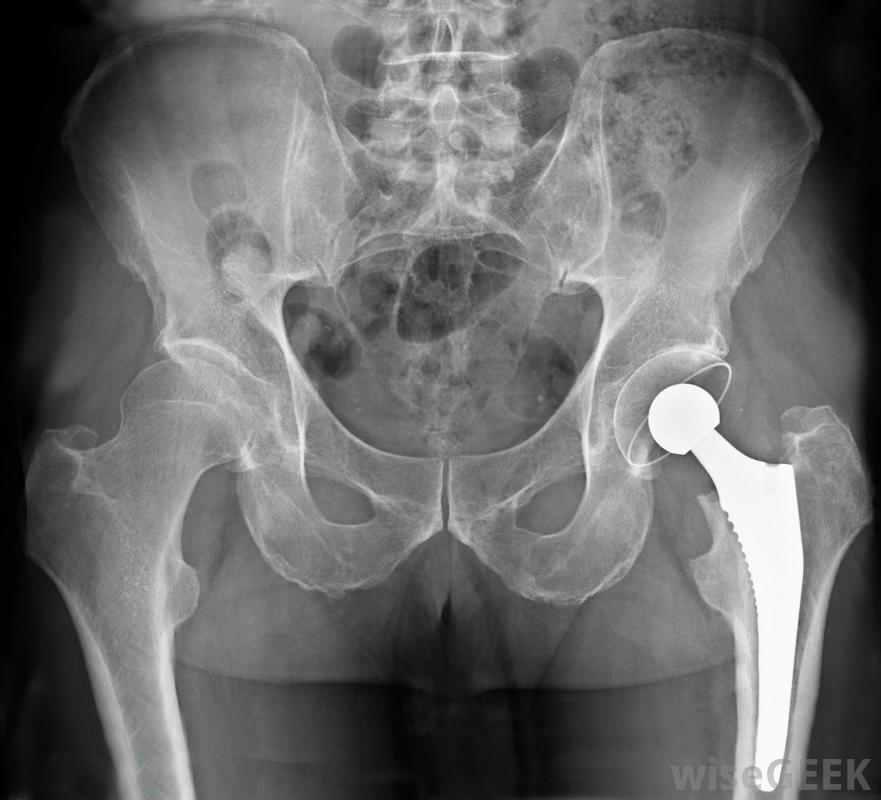

骨盆区域的X光片显示金属置换髋关节。